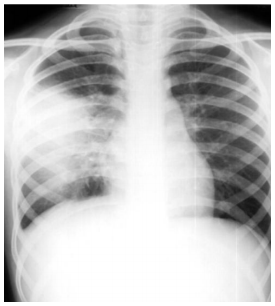

Paciente de 37 anos de idade, procura UPA referindo apresentar há dois dias mal estar geral, dor torácica ventilatório dependente à D e tosse produtiva, com expectoração amarelada e febre aferida 38ºC. É hipertenso, em uso de losartan. Ao exame físico apresenta-se lúcido, orientado, pouco dispneico, com mucosas normocoradas, hidratadas, escleróticas anictéricas; ao exame pulmonar apresenta aumento do frêmito toracovocal em terço médio de hemitórax D, onde ausculta-se um sopro tubário; ritmo cardíaco regular em dois tempos com bulhas normofonéticas, sem sopros. Abdome flácido, ausência de visceromegalias. Membros inferiores sem alterações. Sinais vitais: PA = 140/80 mmHg, FR = 24 irpm, FC = 92 bpm e temperatura axilar = 37,8ºC. Foi realizado RX de tórax no atendimento, o qual é mostrado abaixo. Assinale a alternativa que corresponde CORRETAMENTE ao ambiente para o tratamento inicial e o antibiótico de escolha.

enunciado 1093889-1